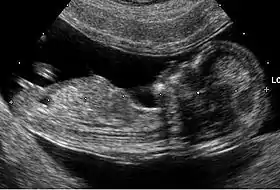

![]() تصویر ثبت شده از جنین در هفته دوازدهم توسط اکوگرافی رحم | |